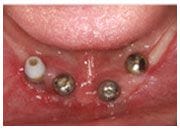

植牙過程

植入植體